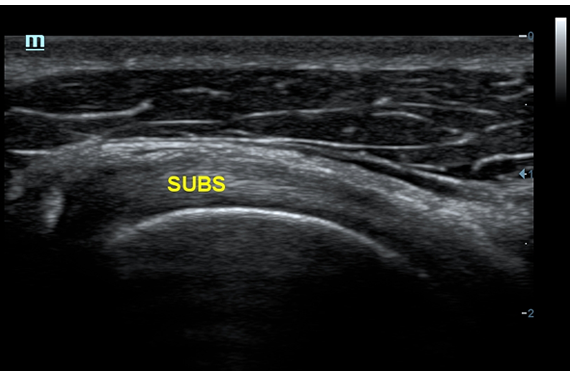

Система ультразвукового исследования Mindray DC-60 EXP X-INSIGHT является новейшей разработкой для проведения комплексных обследований на высшем уровне. Она обеспечивает решение самых сложных задач в таких областях, как кардиология, акушерство и гинекология, сосудистые заболевания, педиатрия и многие другие.

DC-60 EXP X-INSIGHT - это современный стационарный УЗИ-аппарат с функцией сенсорного управления и очищенной гармонической визуализацией, обеспечивающей лучшее контрастное разрешение и технологию 4D-визуализации. Он оснащен 21,5-дюймовым монитором, который может поворачиваться на 180 градусов, что удовлетворяет потребности врачей в качественной ультразвуковой диагностике.

• Поддержка режимов сканирования B/M/Цветовой доплер CDI/Цветной M/Энергетический доплер PD/Направленный энергетический доплер Dir.PD.